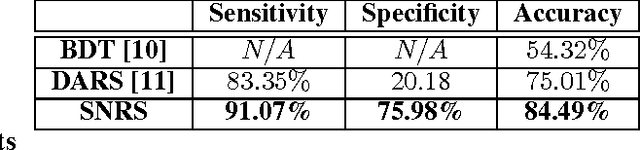

Discovery Radiomics via StochasticNet Sequencers for Cancer Detection

Nov 11, 2015

Radiomics has proven to be a powerful prognostic tool for cancer detection, and has previously been applied in lung, breast, prostate, and head-and-neck cancer studies with great success. However, these radiomics-driven methods rely on pre-defined, hand-crafted radiomic feature sets that can limit their ability to characterize unique cancer traits. In this study, we introduce a novel discovery radiomics framework where we directly discover custom radiomic features from the wealth of available medical imaging data. In particular, we leverage novel StochasticNet radiomic sequencers for extracting custom radiomic features tailored for characterizing unique cancer tissue phenotype. Using StochasticNet radiomic sequencers discovered using a wealth of lung CT data, we perform binary classification on 42,340 lung lesions obtained from the CT scans of 93 patients in the LIDC-IDRI dataset. Preliminary results show significant improvement over previous state-of-the-art methods, indicating the potential of the proposed discovery radiomics framework for improving cancer screening and diagnosis.